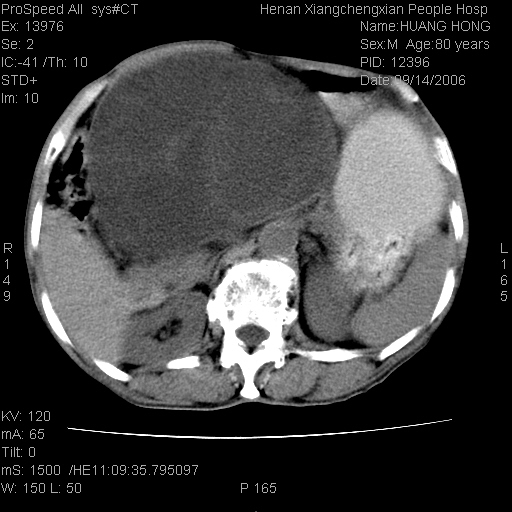

患者, 男, 80岁, 发现上腹部包块1年余,无其它不适.2006-9-14ct片是喝水后扫描2006-9-15ct片没喝水扫描![]() ![]() ![]() ![]() ![]() ![]() ![]() ![]() ![]() ![]() ![]() ![]() ![]() ![]() ![]() ![]() 以上是喝水片 以下是空腹片 ![]() ![]() ![]() ![]() ![]() ![]() ![]() ![]() ![]() ![]() ![]() ![]() ct:胰腺前方、肝脏与胃之间可见巨大类圆形囊性低密度影,大小约152mmx145mmx118mm,上缘平t11椎体上缘,下缘平l3椎体下缘,密度均匀,ct值15hu,其内呈多房分隔,囊壁薄且光滑,边界清晰,周围组织及器官明显受压。肝脏实质内未见异常密度影,胆囊未见异常,胰腺密度未见异常,脾脏大小、形态及密度未见异常,腹膜后间隙未见肿大淋巴结影。 印象:胰腺前方、肝脏与胃之间巨大类圆形囊性低密度影.性质待定。多考虑:.肠系膜巨大囊肿。 守望可可西里发言:支持楼主,考虑肠系膜囊肿,多为小肠系膜。 ysxyy发言:我总觉得这个病人虽然很像肠系膜囊肿,但还是应该强化一下; 下面这几幅图里肿块和主动脉的关系不太清,不知能否除外血管性来源? ![]() ![]() ![]() 病理结果:横结肠系膜间叶瘤.部分区域间质细胞增生活跃. 病理图片 ![]() 良性间叶瘤:是指由两种或两种以上的间叶组织所构成的混合性肿瘤.肿瘤仅发生在腹膜后和肠系膜,.前者较后者多发.良性间叶瘤常发生在肾或四肢,腹膜后较少见,各年龄均可发病.女多与男,预后较好,但术后易复法. 恶性间叶瘤:由两种以上恶性间叶组织成分组成. 光镜:肿瘤由脂肪/血管/平滑肌构成. 原贴地址: http://www.radinet.com.cn/forum_view.asp?forum_id=4&view_id=16217 ok |